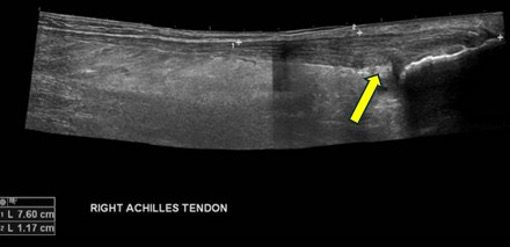

Achados ultrassonográficos na deformidade de Haglund

- Exostose calcânea posterossuperior (a “protuberância”).

- Pode ser visto esporão calcâneo subjacente.

- Espessamento focal na inserção (normal: 4–6 mm; >7–9 mm ou mais sugere patologia).

- Perda da ecotextura fibrilar normal — parece hipoecoico e inchado.

- Tendinopatia insercional e/ou rupturas de espessura parcial.

- Hiperemia ao Doppler na inflamação crônica/ativa.

- Bursa retrocalcânea: Distensão anecoica ou hipoecoica (acúmulo de líquido).

- Bursa superficial/subcutânea: edema hipoecoico entre a pele e o tendão. Ambas as estruturas podem parecer aumentadas e inflamadas.

- Convexidade dos tecidos moles posteriores ao tendão (bursite superficial).

- Interface rompida onde o tendão encontra o calcâneo.

A ultrassonografia é uma modalidade altamente eficaz para avaliar ou diagnosticar a deformidade de Haglund e a síndrome de Haglund, além de auxiliar na definição de patologias ósseas e de tecidos moles ao redor da inserção do calcâneo. Os principais achados incluem uma protuberância calcânea posterossuperior, tendão espessado e hipoecoico, bursite retrocalcânea e superficial e aumento do fluxo Doppler em casos de inflamação ativa.